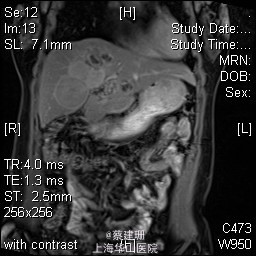

主诉:平滑肌肉瘤、肝转移癌术后,发现肝多发转移2月余。 现病史:患者3年前外院检查发现后腹膜肿瘤,外院行后腹膜肿瘤切除术后,术后病理为:平滑肌肉瘤,2013年12发现肝左叶转移癌,外院行肝左叶肿瘤切除术,术后病理为:梭行平滑肌肉瘤。2月余前患者复查发现肝脏多发转移,2015-4月肝脏MRI:肝脏多发转移。现患者无恶心、呕吐,无呕血、黑便,无皮肤巩膜黄染,无剧烈腹痛发作。现为进一步诊治收住入院。

查体:锁骨上淋巴结未扪及肿大;腹部平坦,可见陈旧性手术疤痕。未见肠型、胃型蠕动波,腹软,无压痛及反跳痛,无肌卫,肝脾肋下未及。Murphy’s 征(-),肝区叩击痛(-),肾区叩击痛(-);移动性浊音阴性。 辅查:2015-4月肝脏MRI:肝脏多发转移。

诊断 :1、多发肝转移癌 2、后腹膜平滑肌肉瘤术后 3、肝转移癌术后 处理:取右侧肋缘下切口,左侧延长,逐层切开进腹,探查腹腔:见上腹部粘连,仔细游离上腹部腹腔粘连,探查见无腹水,胃、肠、胰、脾及盆腔脏器未及异常,腹腔未见明显转移结节;肝脏无硬化。肝门淋巴结无肿大,门静脉主干无栓子。肿瘤多枚,最大两枚位于肝右叶VI段,肿瘤大小约7*6*5cm。V段肿瘤直径约5cm。左内叶肿瘤多枚,直径0.5-4cm,紧贴第一肝门。左外叶肿瘤多枚,直径1-3cm,肿块质韧,边界尚清,有包膜。术中诊断为转移性肝癌,决定行左半肝切除,肝右叶特殊肝段切除。